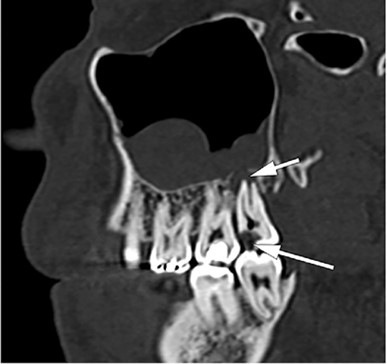

Odontogenic sinusitis most commonly develops as a result of infections originating from the upper jaw (maxilla) posterior teeth spreading to the maxillary sinus. The roots of the upper posterior molar teeth are very close to the sinus floor in most people. In some individuals, the tooth root can extend directly into the sinus. Therefore, tooth root infections, failed root canal treatments, periapical abscesses, oroantral fistulas formed after tooth extraction, sinus lifting procedures, and dental implants can lead to maxillary sinusitis.

Particularly in unilateral sinusitis lasting longer than 3 months, paranasal sinus CT imaging is important.